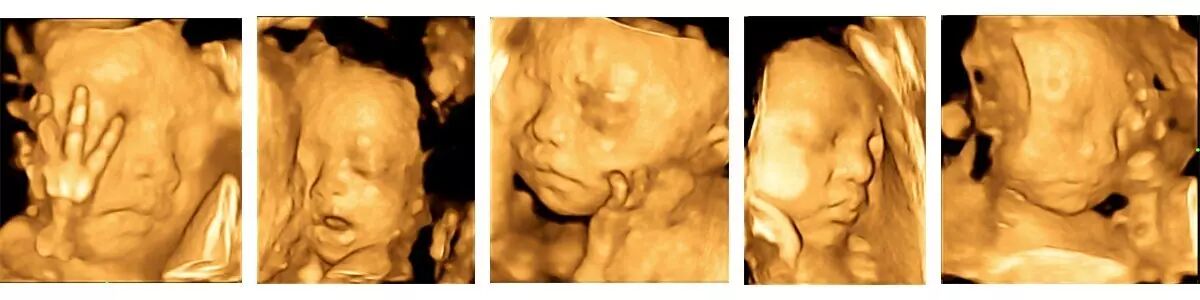

滨州百佳妇产医院引进的美国GE实时超声影像系统以及被誉为“神奇彩超“的GE-E8,超越传统超声的限制,不仅能够检查传统的胎儿生理指标,还可以360°立体展示胎儿各器官的发育情况,对胎儿解剖结构、健康发育状况的检查更为详细,还能将胎儿在母亲腹中的运动过程形象展示。为准妈妈制作一份独一无二的胎儿宫内高清动态写真,这将是无比美好的孕期纪念,也是送给未来宝宝的珍贵礼物。

胎儿面部:如唇愕裂等